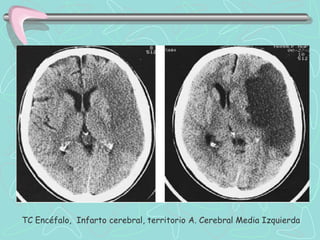

TOMOGRAFÍA COMPUTARIZADA DE ENCÉFALO

•Examen de elección en el Ictus agudo

ICTUS ISQUEMICO

•Aguda : lesión hipodensa.

•Subaguda (2º semana) Hipodensidad se intensifica

La detección precoz de imágenes hipodensas (menor

a 24 h) tienen pronóstico ominoso,

SIGNOS PRECOCES DE ICTUS ISQUÉMICO AGUDO

•1. Hipoatenuación de cinta insular

•2. Oscurecimiento del núcleo lenticular

•3. Hipodensidad / borramiento cortical

•4. Hiperdensidad de la ACM

TC Encéfalo, Infarto cerebral, territorio A. Cerebral Media Izquierda